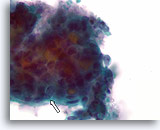

Afbeelding 52

Folliculair neoplasma, schildklier FNA, celblok.

Immunokleuring voor cytokeratine 19 is negatief. Hoewel er geen definitieve markers zijn voor papillair schildkliercarcinoom. helpt de afwezigheid van cytokeratine 19 enigszins bij de uitsluiting van papillair schildkliercarcinoom. Reactieve veranderingen die kunnen lijken op papillair schildkliercarcinoom zijn vaak positief voor cytokeratine 19; positieve kleuring moet dus voorzichtig worden geïnterpreteerd.

20X

Afbeelding 52

Folliculair neoplasma, schildklier FNA, celblok.

Immunokleuring voor cytokeratine 19 is negatief. Hoewel er geen definitieve markers zijn voor papillair schildkliercarcinoom. helpt de afwezigheid van cytokeratine 19 enigszins bij de uitsluiting van papillair schildkliercarcinoom. Reactieve veranderingen die kunnen lijken op papillair schildkliercarcinoom zijn vaak positief voor cytokeratine 19; positieve kleuring moet dus voorzichtig worden geïnterpreteerd.

20X